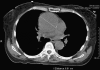

Acute aortic dissection is a medical emergency. Without prompt recognition and treatment, the mortality rate is high. An atypical presentation makes timely diagnosis difficult, especially if the patient is experiencing no characteristic pain. Many patients with aortic dissection are reported to have presented with various neurologic manifestations, but none with only a presentation of transient locked-in syndrome.Herein, we report a case of completely painless aortic dissection in a woman who presented with a transient episode of anarthria, quadriplegia, and preserved consciousness. On physical examination, she had a 40-point difference in blood pressure between her left and right arms, and a loud diastolic murmur. The diagnosis of acute aortic dissection was reached via a combination of radiography, computed tomography, echocardiography, and a high index of clinical suspicion. The patient underwent emergency surgery and ultimately experienced a successful outcome.To our knowledge, this is the 1st report of aortic dissection that presented solely as locked-in syndrome. We suggest that silent aortic dissection be added to the differential diagnosis for transient locked-in syndrome.